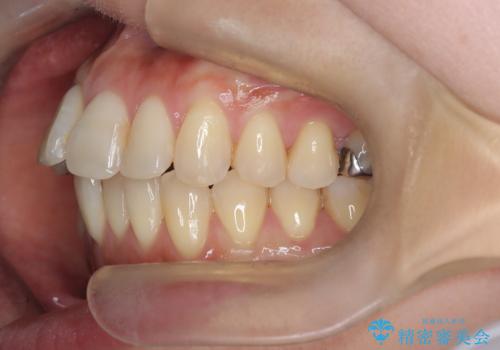

半年で改善した上顎前歯の突出

- 患者様は、上顎前歯の突出を改善したいとのご希望で来院されました。診断の結果、噛み合わせや全体的な歯列には大きな問題がないため、上顎のみを対象とした部分矯正が最適と判断しました。特に患者様は短期間での治療完了を希望されていたため、治療期間を約半年と設定しました。審美ワイヤーを用い、前歯を後方に移動させることで、自然で整った仕上がりを目指しました。治療計画は、患者様のスケジュールや希望を最大限考慮し、実現可能な目標を設定しました。

部分矯正では、治療範囲が限定されるため、力のコントロールが非常に重要です。本症例では、前歯を後方に移動させる際、周囲の歯や噛み合わせに影響を及ぼさないように細心の注意を払いました。また、短期間の治療でも歯の移動に伴う歯肉や歯根への負担を抑えるため、定期的なチェックと調整を行いました。患者様には矯正装置の清掃を徹底していただき、虫歯や歯周病のリスクを回避しました。結果として、予定通りの期間で治療を完了し、患者様には満足していただけました。